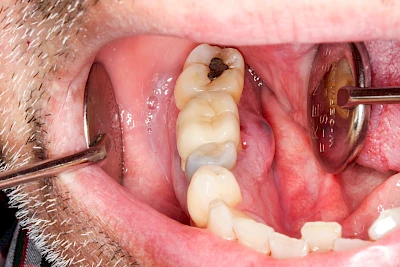

Ist zunächst nur das Zahnfleisch von der Entzündung betroffen, spricht man von Gingivitis. Später, wenn auch der Knochen um die Zähne herum entzündet ist, spricht man von einer Parodontitis. Bei der Parodontitis wird der Knochen nach und nach abgebaut und das Zahnfleisch zieht sich zurück. Die Zahnhälse und Zahnwurzeloberflächen liegen mehr und mehr frei. Die Zähne werden zunehmend lockerer und fallen schließlich aus.

Bei Implantaten – also operativ eingebrachten künstlichen Zahnwurzeln – kann der Körper die Bakterien auch nicht so gut abwehren. Hier spricht man im Fall einer Entzündung von einer Peri-Implantitis, also einer Entzündung um das Implantat herum.